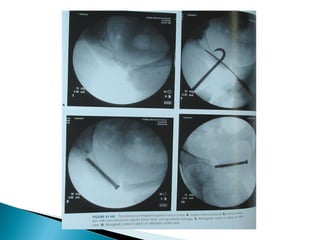

 Intraoperative fluoroscopic imaging even during

initial resuscitation of patient there by

diminishing pelvic bleeding.

 Most successful when performed within 5 days

after injury

 Anterior pelvic fixation the most common form

of percutaneous fixation, while diminishing

operative blood loss and operative time.

 SI joint disruption:

A full threaded 6.5mm cancellous screw is passed from ilium

perpendicular to and across S1 joint (or sacral fracture) through

sacral ala terminating within the body of S1 vertebra.